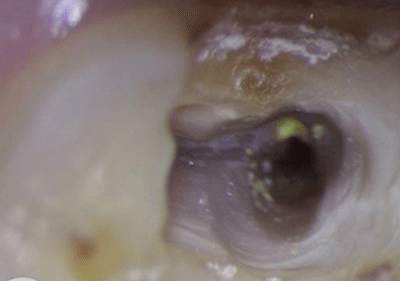

术中显微镜根管探查

显微根管治疗器械的应用,能够更清楚地看到髓腔根管系统的细微结构,使临床操作更准确,手术视野更清晰,治疗成功率更高!